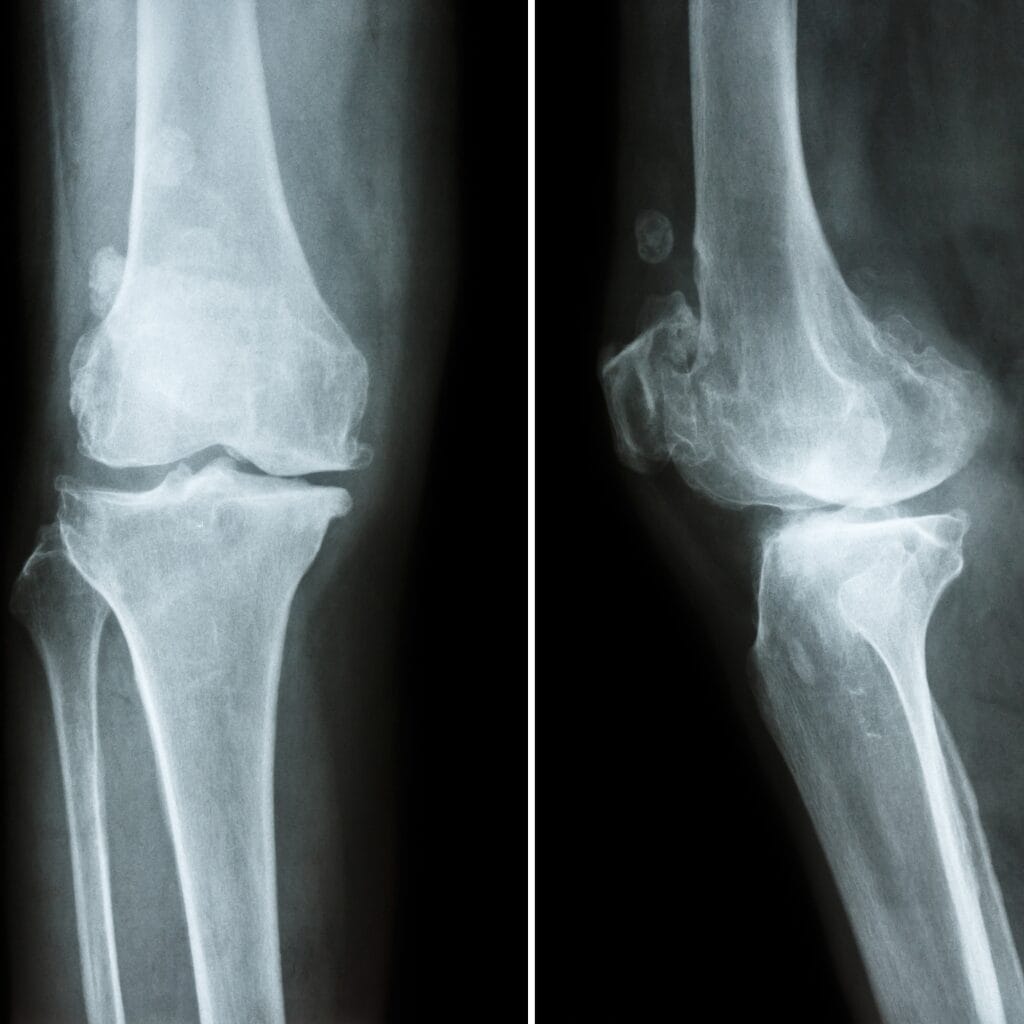

Contrairement à l’arthrite (inflammation articulaire d’origine immunitaire), l’arthrose est d’abord une dégénérescence mécanique : le cartilage s’use plus vite qu’il ne se régénère. Mais avec le temps, cette usure déclenche aussi une inflammation locale, qui aggrave les douleurs et la dégradation articulaire.

- Elle concerne 1 personne sur 2 après 65 ans, mais peut commencer bien plus tôt.

- Elle touche souvent les genoux, hanches, colonne vertébrale, mais aussi doigts, poignets, épaules…